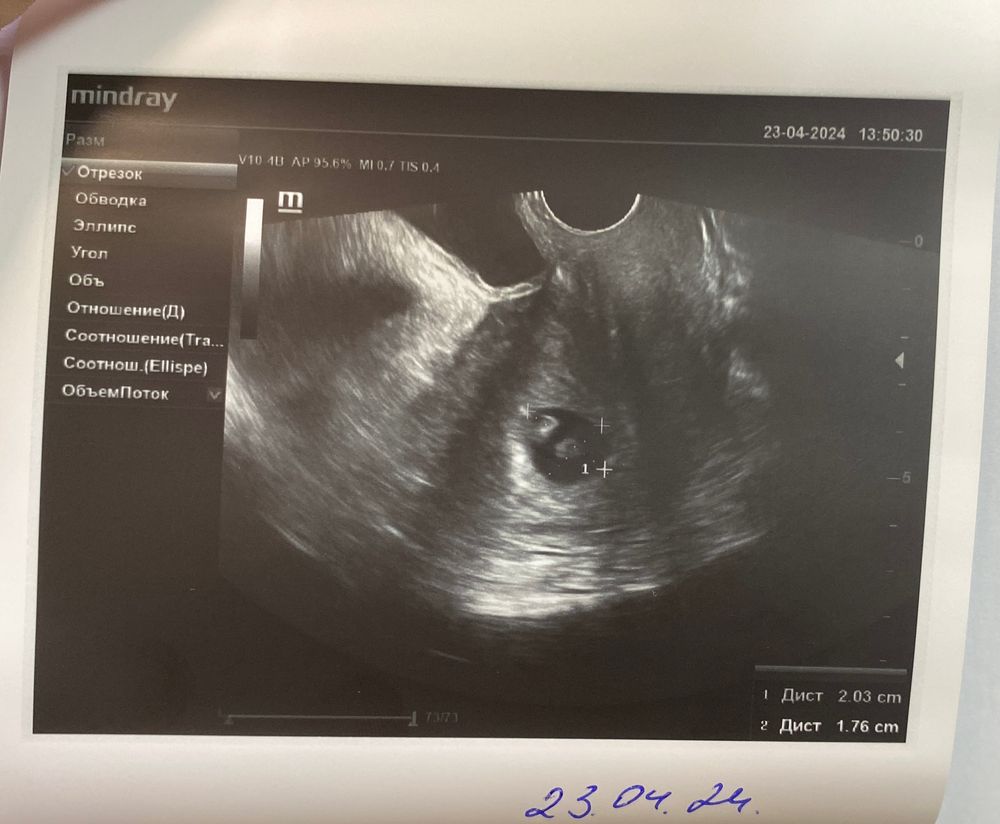

Нам 6 недель✨

такой маленький червячок, а любовь к тебе уже большая😘

Спасибо что выбрал нас 🥹✨ Скоро первый скрининг 😄🔥